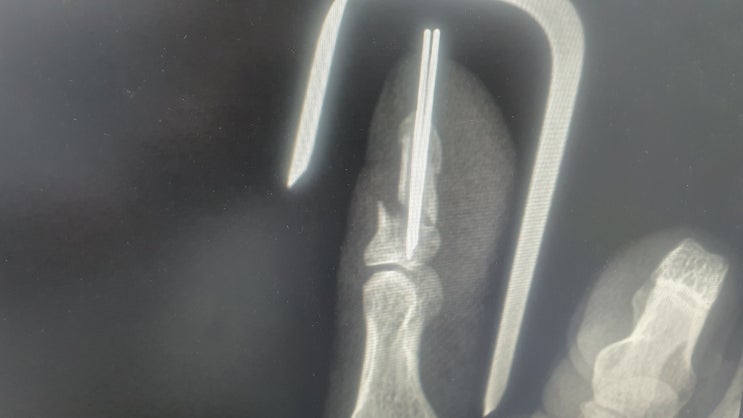

오전에 왕복 3시간 도시 병원 외래진료 다녀와-뼈는 잘 생성 중임. 염증 생길 수 있다고 핀 제거 전까지 물...

지겨운 병원생활 청산하고 퇴원했건만 엄지손가락 고정 핀 2개 제거하려면 한 달은 더 기다려야 한다고......

[지금 나의 모습] 안전사고 유의하세요~

세상이 망했구나 이제 끝이군! 거울 보면 아마도 이런 표정일 듯. 작업 전 안전장구 착용 소홀히 하지 않고...